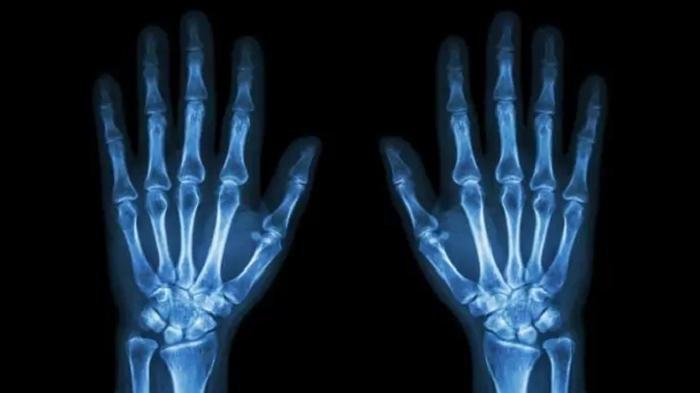

Jangan berlebihan konsumsi beberapa makanan dan minuman ini, agar tulang tetap sehat